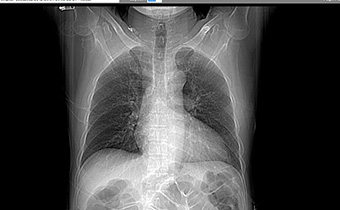

간질성 폐렴이 완전히 치료되었습니다.

이** (50대)13.09.03